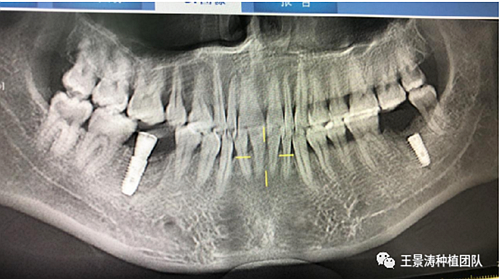

患者左側(cè)16慢性根尖周炎,17缺失。16根尖炎癥距上頜竇底較近,需內(nèi)提升,但是因?yàn)閮?nèi)提升后骨質(zhì)較薄所致植入深度過深,埋入式植入。17非埋入式種植。后期效果均可。

術(shù)后一周

二期手術(shù)